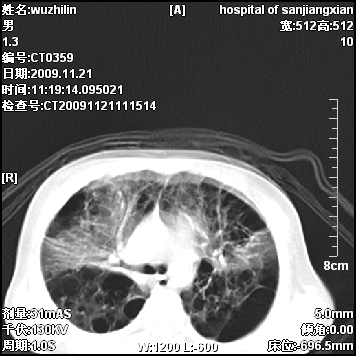

标题: PED3072: 1岁3个月患儿 胸部弥漫性病变 [打印本页]

标题: PED3072: 1岁3个月患儿 胸部弥漫性病变

弥漫性薄壁囊腔,胸膜下及肺底部占优势,双上肺磨玻璃密度影,首先考虑特发性肺间质纤维化,其次囊性肺纤维化,肺淋巴管平滑肌瘤病嗜酸性肉芽肿等;要结合临床综合考虑。

两肺布满多个薄壁含气囊腔,以下肺居多,伴磨玻璃样密度影,左侧气胸。两肺发育不全、两肺多发肺囊肿并感染,其次考虑肺囊腺瘤。